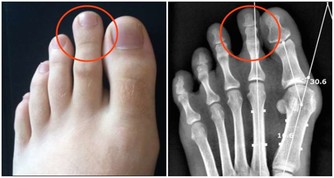

雖然螃蟹的營養價值高,但蟹膏和蟹黃含膽固醇較多,建議腎病、痛風、高脂血症患者,不要多吃。